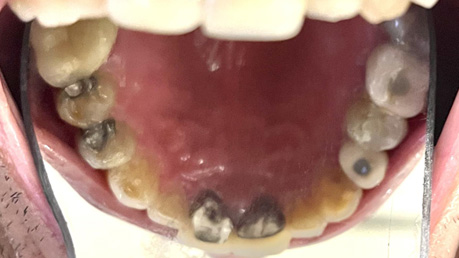

Patient Intraoral Photographs

- Mandible

Dental Hygiene: The patient has osteoarthritis and cannot perform oral hygiene on himself. At the first appointment, he revealed he has a PSW that brushes for him using a manual toothbrush with Crest toothpaste 0.454% Stannous fluoride (1100 ppm fluoride) twice daily (morning before breakfast and before bedtime). No other fluoridated products are used at home. He consumes fluoridated tap water and does not use mouthwash. Fluoride varnish has been applied to his teeth at scaling and root planing (SRP) appointments. Currently, he has only been getting SRP once a year as a preventative procedure. His latest SRP was in October 2023 when I first saw the patient. During his last SRP appointment, there was heavy generalized plaque and supragingival calculus, moderate generalized subgingival calculus, and bleeding on probing (BOP) localized to the mandibular anterior teeth. The gingiva was red and inflamed throughout the mouth. The interproximal areas and gingival third of the teeth were often missed during his at-home oral hygiene regimen. The patient states the PSW brushes with horizontal strokes for less than 30 seconds each day. The patient states that he gets flossed every other day or every 3-4 days, but this did not correspond to what was seen clinically. He appeared motivated to attain better oral hygiene, but he states his PSW is not motivated to brush his teeth for longer durations and is reluctant to provide him with oral hygiene (OH) unless he requests for it daily. The patient has no family history of oral cancer, has never smoked, does not consume alcohol, does not use chewing tobacco, and does not excessively expose himself to the sun.

Carious Lesions: 12MV, 13DV, 14MOV, 25O, 31V, 42MV, 45V

Habits: The patient is a bruxer and attrition can be seen particularly in the mandibular anterior teeth. He wears a nightguard each night for 6-8 hours.